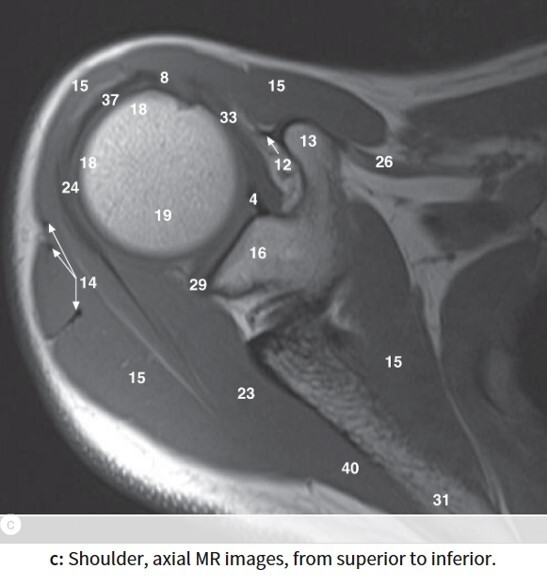

4

Q

Label 13,15,16,18,19,23,32

A

13=Rt. coracoid process

15=Rt. deltoid muscle

16=Glenoid process of Rt. scapula

18=Greater tubercle of Rt. humerus

19=Head of Rt. humerus

23= Rt. infraspinatus muscle

32=Rt. subscapularis muscle